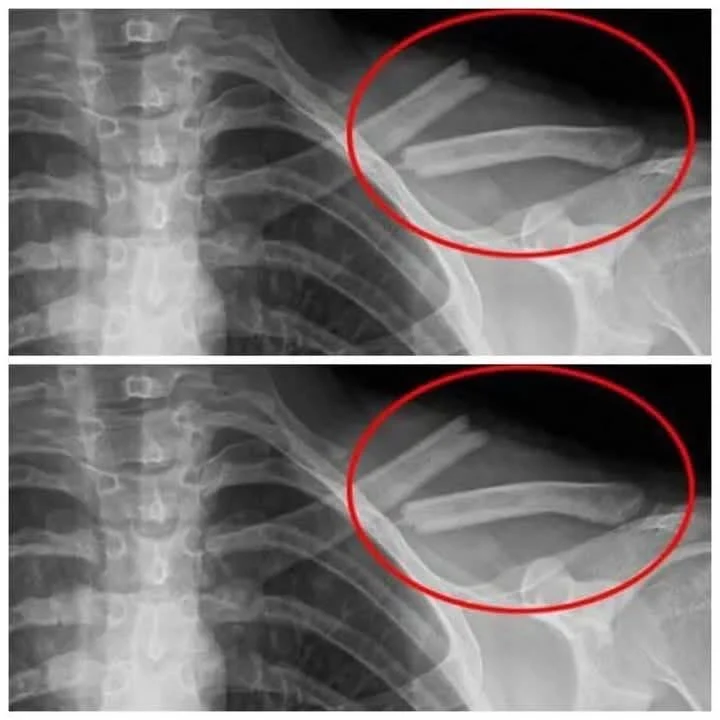

- Bone Weakening: High soda intake depletes calcium, increasing osteoporosis risk.